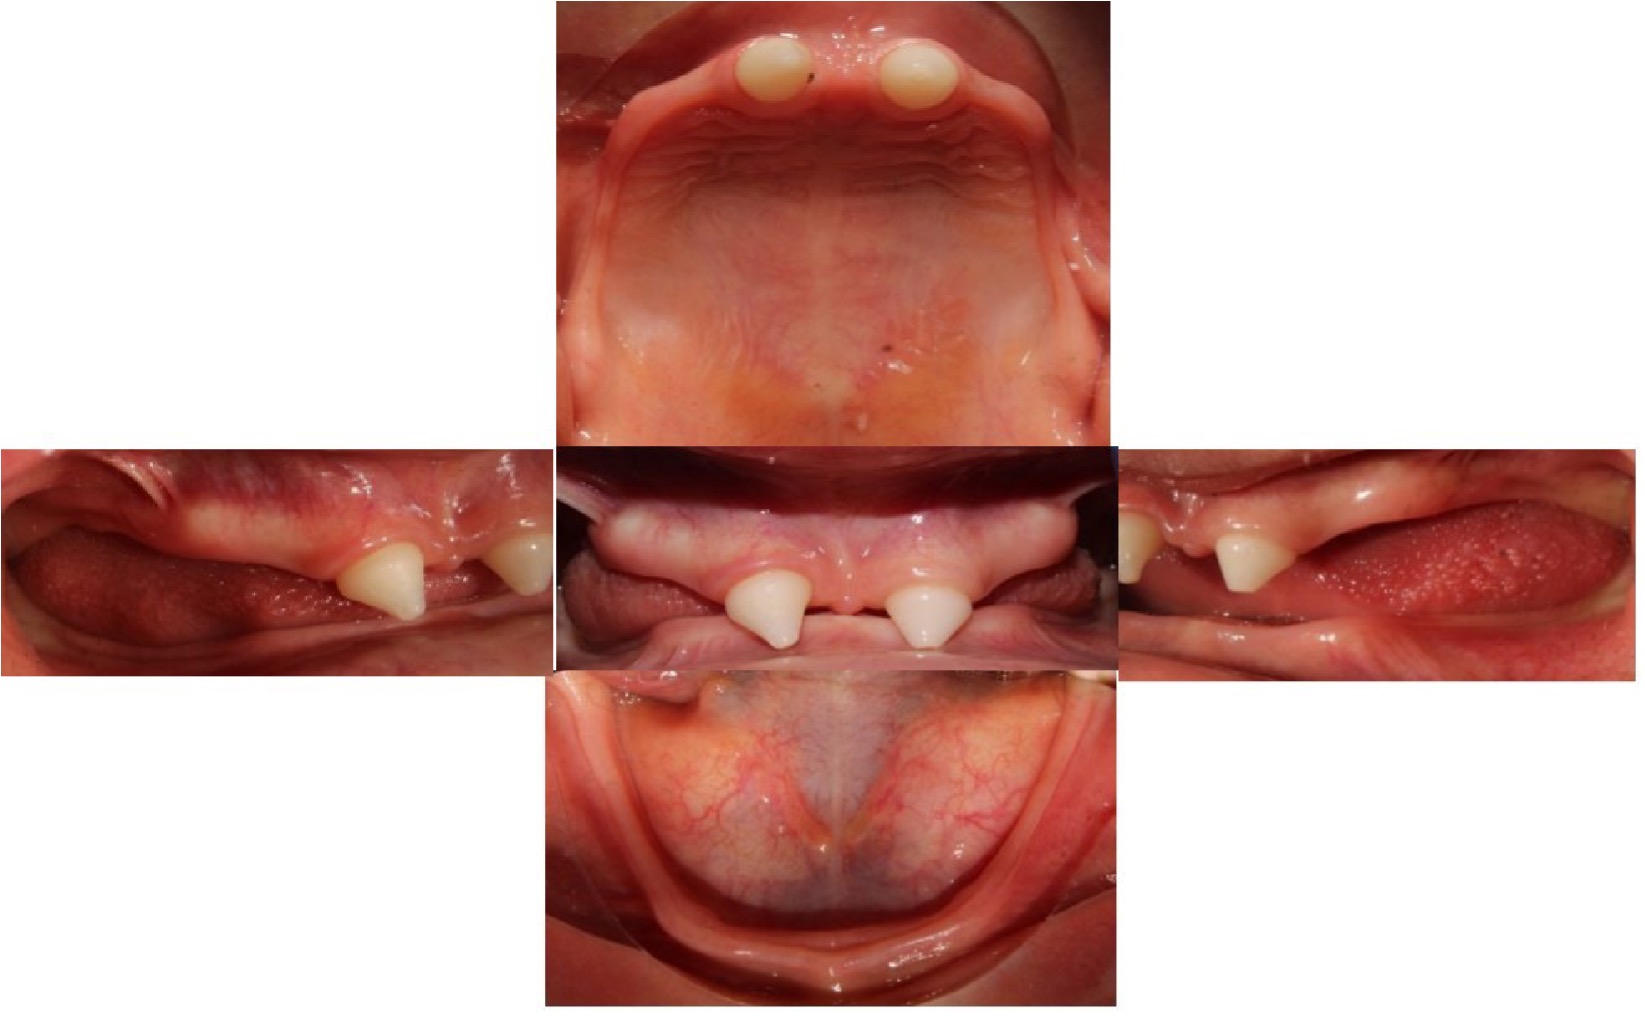

Una vez que el laboratorio nos entregó las coronas de disilicato de litio, se probaron en boca y se acondicionaron los dientes y las coronas de acuerdo al protocolo establecido para coronas de disilicato de litio, en el que se debe acondicionar las coronas con ácido fluorhídrico (Porcelain Etch de Ultradent®) por 20 segundos, posteriormente se enjuaga y se coloca ácido fosfórico al 35% (Ultra-Etch de Ultradent ®) durante 1 minuto, se enjuaga nuevamente y se aplica silano (Silane de Ultradent®) por 1 minuto; posteriormente se realiza profilaxis de los dientes y se acondicionan con ácido fosfórico al 35% (Ultra-Etch de Ultradent®) durante 10 segundos, se lava y se coloca adhesivo (Futurabond NR de Voco), se realizó fotocurado por 20 segundos, se cementaron con cemento resinoso dual (Maxcem EliteTM de Kerr ) y se fotocuró nuevamente durante 20 segundos por cada cara (Figura 8). Se le dieron indicaciones sobre los cuidados de las coronas. En cuanto a las prótesis removibles, se suministraron las indicaciones al paciente y a su madre acerca del cuidado de las prótesis, el uso de crema adhesiva para prótesis (Ultra Corega de GSK). Además, se indicó dar 1⁄4 de vuelta a la semana al tornillo de ambas prótesis para estimular el crecimiento y mejorar la conformación de ambas arcadas (Figura 10).

Se obtuvieron resultados satisfactorios en el momento de concluir la rehabilitación bucal, mejorando la autoestima del paciente, se puede observar que en la fotografía de sonrisa inicial (Figura 1) presentaba una clasificación de “sonrisa Mona Lisa”, caracterizada por la acción de los músculos cigomáticos mayores, moviendo las comisuras hacia afuera y arriba, seguido de una elevación gradual del labio superior,17 sin exposición dentaria, al contrario de la fotografía final de sonrisa (Figura 9) donde se mostró una sonrisa franca con exposición dental, resultando de la contracción de todos los músculos elevadores y depresores de los labios y de las comisuras. Se evidencia una mayor estética, su cara es más armónica, percibimos un aumento en el tercio inferior de la cara de 29,8% a 32,2%; observándose un equilibrio de los tercios faciales y mejorando el perfil inicial superior en 3 mm y el inferior en 0 mm (Figura 9).

Figura 10: Fotografías intraorales finales

En el seguimiento a los 2 meses se observó una mejor adaptación y retención de las prótesis, debido a que el paciente refirió no necesitar la utilización de adhesivo (Ultra Corega de GSK); de igual manera, se evidenció una mejor función masticatoria debido al reporte de la madre que indica que el niño ya puede masticar diversos alimentos más duros como la manzana sin trocear. Por otra parte, hubo una mejoría en la fonación, debido a que anteriormente no pronunciaba casi ninguna palabra y a los dos meses ya no tiene problemas en pronunciar palabras con las letras T, P, C, K y mejorando la pronunciación de palabras con G, R, S, F, por lo que se recomienda continuar su proceso se terapia de lenguaje.